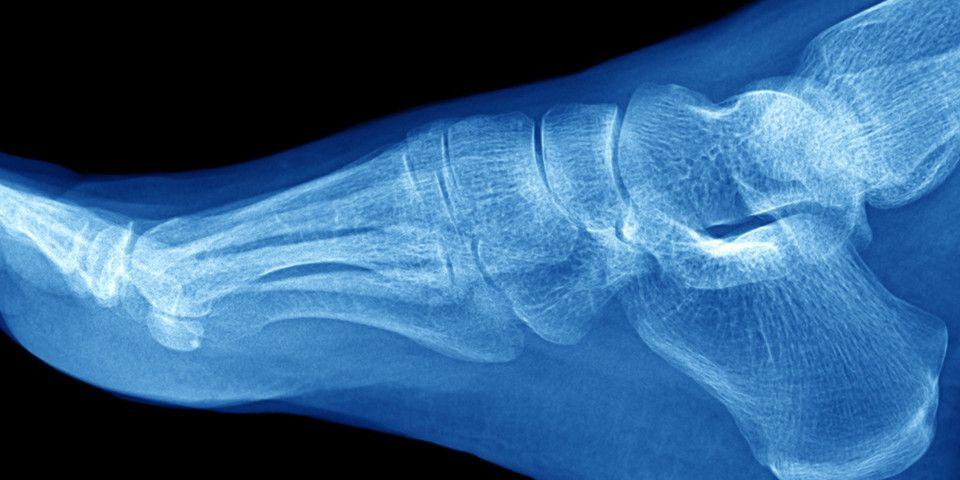

In order to actually understand what an ankle sprain is, it is helpful to first understand the fundamental anatomy of an ankle sprain. There are four ligaments in the ankle, and these fibrous-bands of tissue connect bone to bone, subsequently providing stability to the joint. If and when these ligaments are stressed beyond their capacity, they can stretch or tear, ultimately yielding a sprained ankle. The diagram below illustrates the most common mechanism of injury and progressive stages of ligament compromise

If no progress is being made after employing conservative measures, including the aforementioned RICE therapy in tandem with anti-inflammatory medication, a trip to your Rothman physician may be warranted. Here in the clinic, a proper evaluation can be performed, leading to an accurate diagnosis and consequently optimal chances of healing. A comprehensive physical examination and imaging studies (X-rays/MRI) are utilized in order to lend the physician insight into the underlying pathology.